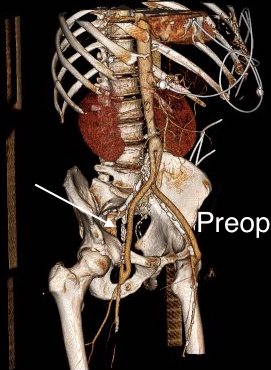

CTA (pictured above and below) showed a 5.1cm infrarenal AAA with an hourglass shaped neck with moderate atherosclerosis in the neck, an occluded left common iliac artery with external iliac artery reconstitution via internal iliac artery collaterals, and a right external iliac artery occlusion with common femoral artery reconstitution. There was calcified right common femoral artery plaque.

Despite these risks, I have performed AUI-FEM-FEM with good results with the modification of deploying the terminus of the stent graft across an end to end anastomosis of the conduit graft to the iliac artery (below), resulting in seal and avoiding the problems of bleeding from the usually heavily diseased artery

The conduit is 12mm in diameter, the key is to deliver the stent graft across the anastomosis, sealing it. The conduit is then sewn to the side of a fem-fem bypass in the pelvis, maintaining antegrade flow to both legs. The other option is to sew the conduit to a 14×7 bifurcated graft. Illustrated above is this 12mm conduit sewn end to end to the diseased common iliac artery with wire access into the aorta and a aorto-uni-iliac device. Typically, a small AUI converter (Cook, Medtronic) can be used, but the aorta is often too small even for a 24mm device, and an iliac limb with a generous sized docking segment (Gore) ending in a 12mm diameter fits nicely. Below is a CTA from such a case, where the stent graft is deployed across the anastomosis, sealing it off from anastomotic leaks (exoleaks).